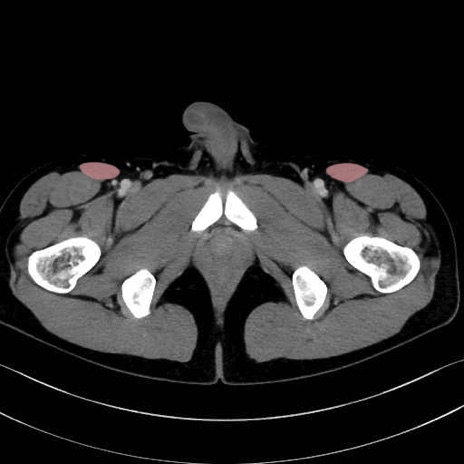

縫工筋 (Sartorius)